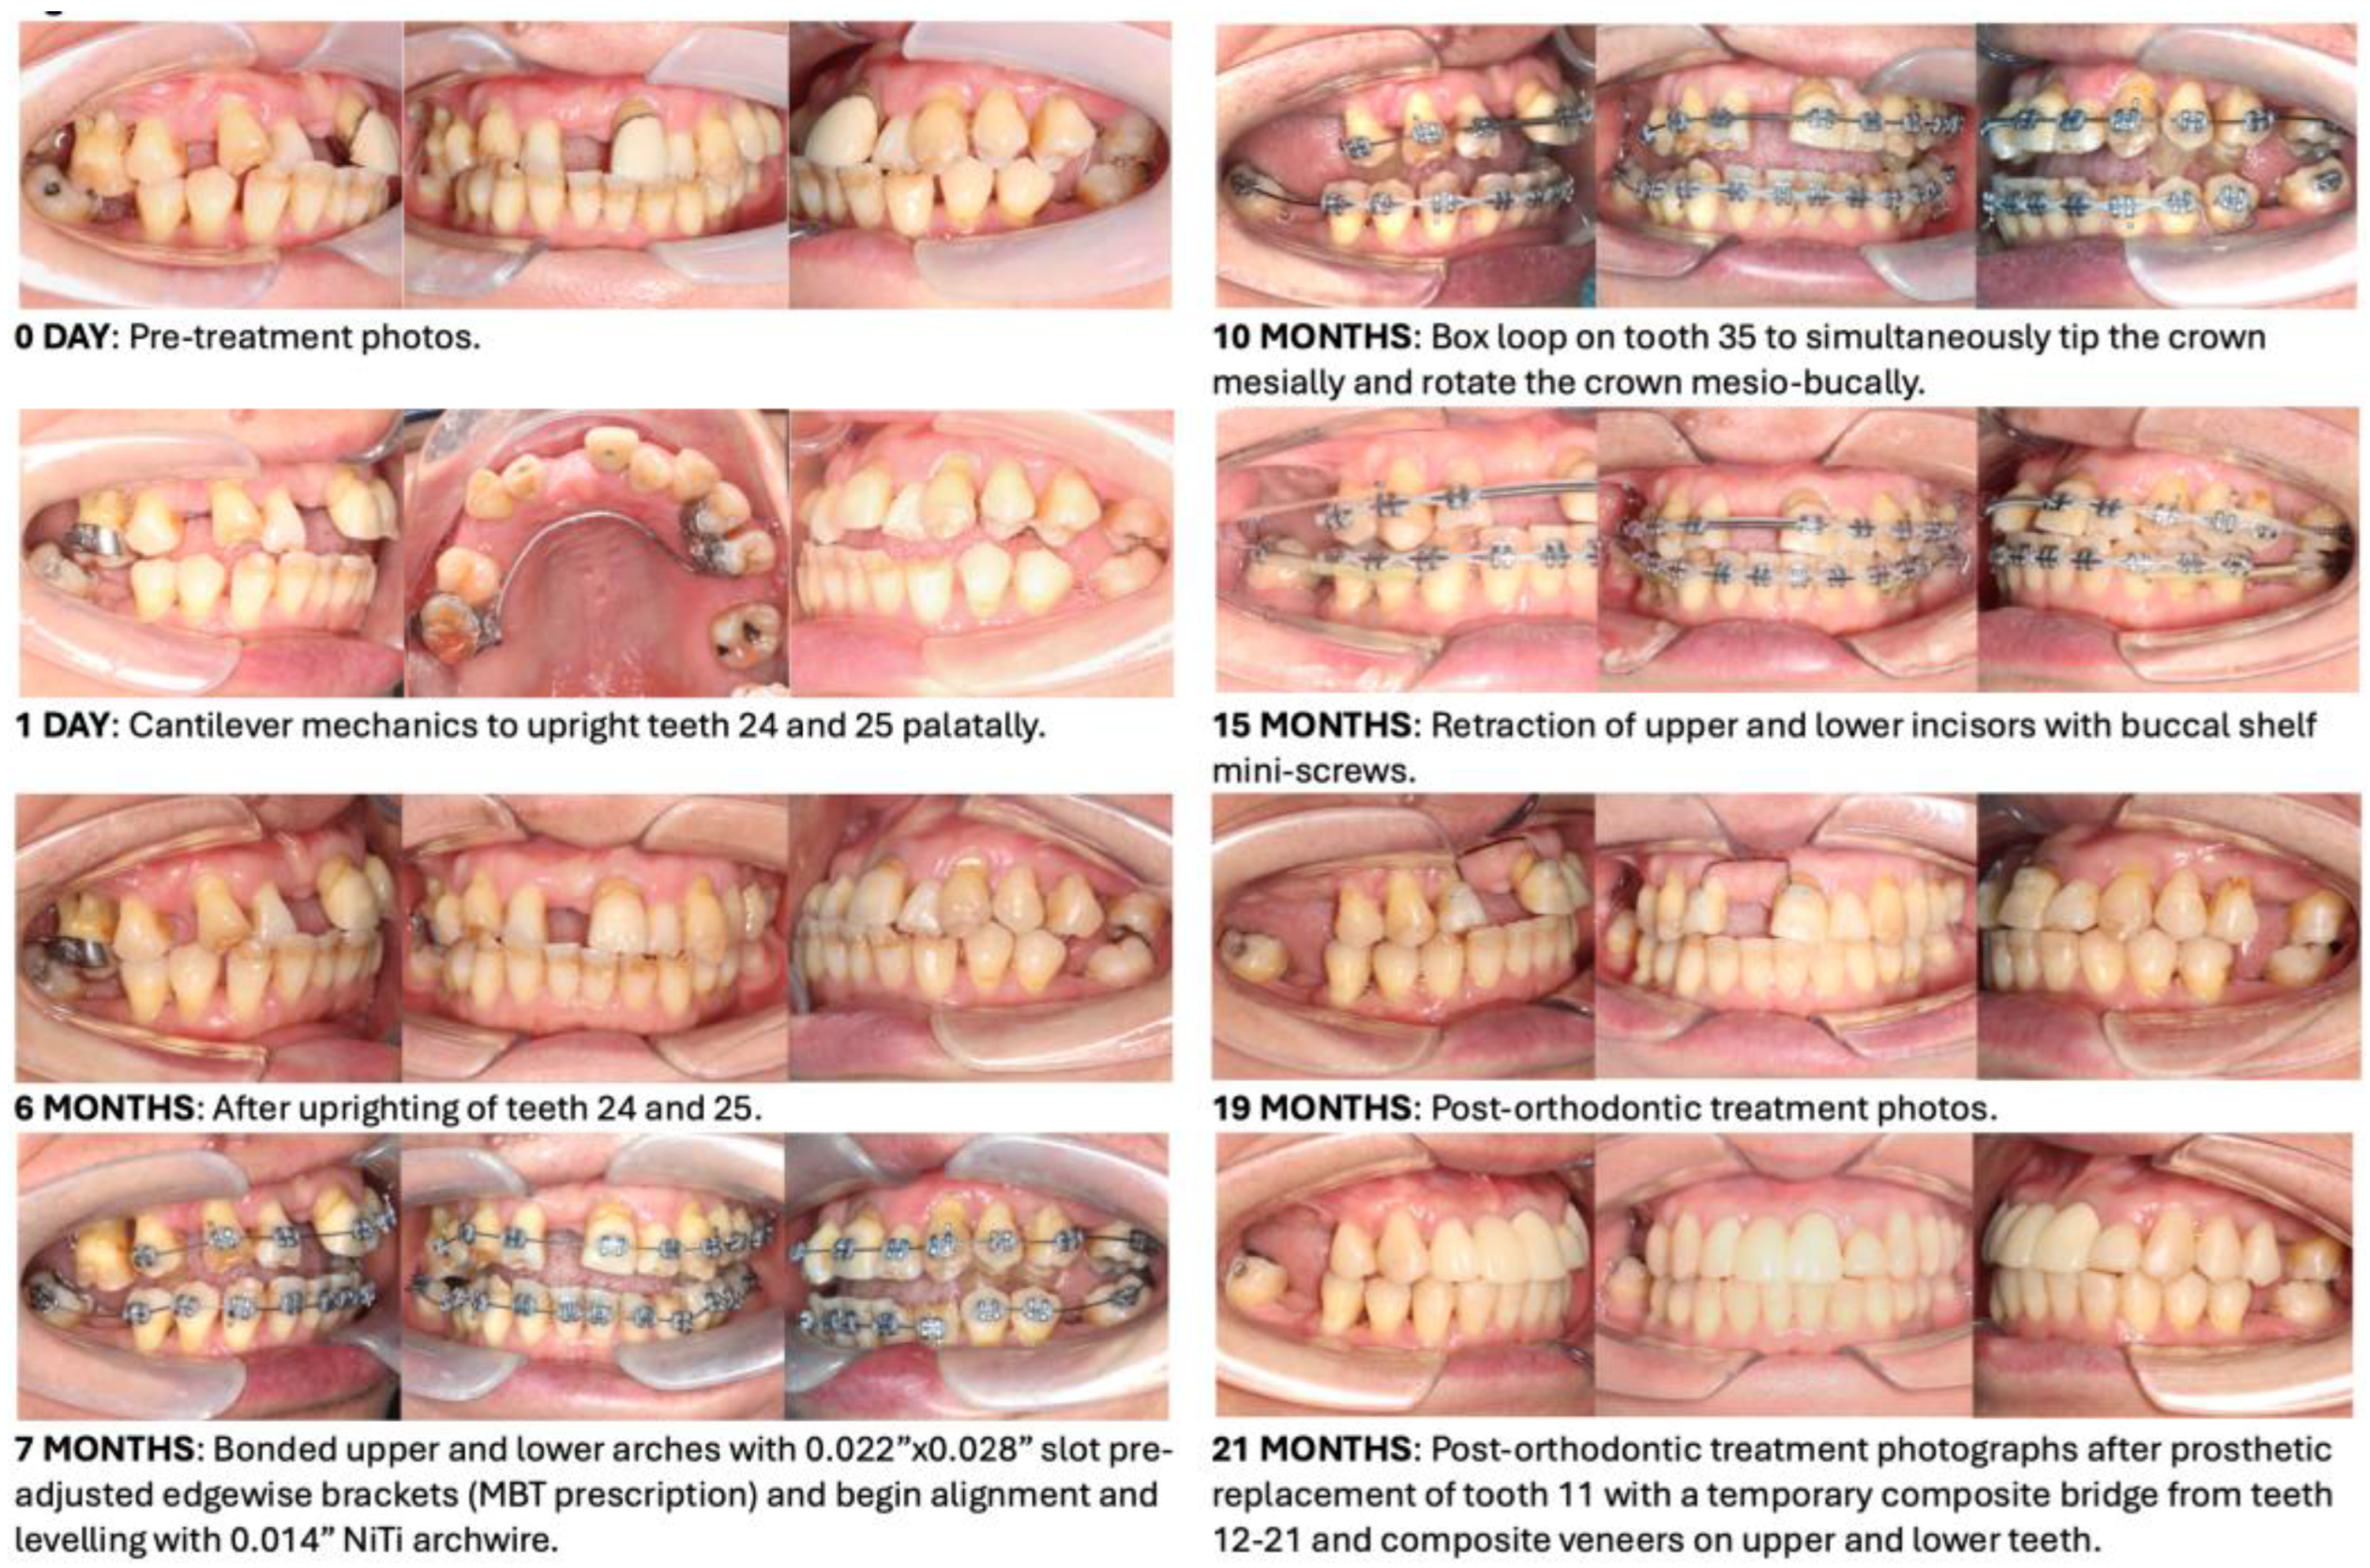

- During the treatment of this patient with Stage IV Grade C generalised periodontitis, we addressed the biomechanical challenges outlined in lists 3.1 to 3.3 at four specific time points.

- (3.4.1)

- As teeth 24 and 25 were significantly buccally displaced, sectional cantilever mechanics were used rather than direct bonding of the entire upper arch. There were two reasons for this. The first reason was to avoid creating unfavourable force systems on the other teeth due to the buccally displaced positions of teeth 24 and 25. Bonding brackets onto all upper teeth and engaging them with a straight wire could have resulted in an abnormal or skewed arch form. The second reason was that tooth 16 had a poor prognosis and was to be extracted in the future. Therefore, we decided to use tooth 16 as free anchorage to bring teeth 24 and 25 into the planned archform with cantilever mechanics, before proceeding with straight wire mechanics.

- (3.4.2)

- During the alignment and levelling stage, tooth 35’s crown was displaced distally and rotated disto-bucally, so a box loop capable of delivering the desired magnitude of force and precisely regulating the force direction was used. The box loop increased the total amount of wire between brackets of teeth 34 and 35, which produced a reduced load–deflection ratio and a greater range of action than any other loop type [41]. Furthermore, as the box loop was composed of a series of vertical and horizontal levers contoured to provide a short section of archwire that was freely movable in all planes in which it was activated, we used it to tip the crown of tooth 35 mesially and rotate tooth 35 mesio-lingually [41]. Moreover, sufficient anchorage was provided by the relatively rigid, continuous wire portion adjacent to the box loop, spanning from teeth 34 to 45, which effectively differentiated the active and reactive units.

- (3.4.3)

- As discussed in list 3.3, periodontally compromised teeth would tip excessively in response to orthodontic force which is applied at the regular bracket level. Therefore, if the aim is to achieve bodily retraction of incisors, it is best to bond the brackets as cervically as possible. However, since the pre-treatment upper and lower incisors were proclined, we aimed to achieve ‘uncontrolled tipping’ during retraction, and thus, the brackets were bonded at the regular positions on the upper and lower incisors [42].

- (3.4.4)

- The attempted placement of mini-screws on the upper alveolar bone resulted in dislodgement due to the low sinus floor. This was caused by sinus peumatization which was a continuous physiological process that increased the volume of the paranasal sinuses [43]. To address this, lower buccal shelf mini-screws were used instead to retract the upper arch with Class I elastics.